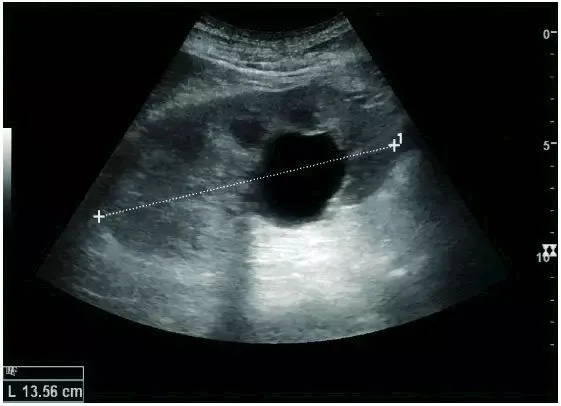

Features of complex renal cysts: septation, calcification, and irregular thickening of the cyst wall. Doppler ultrasonography is feasible for further evaluation. Bosniak grading and follow-up of complex renal cysts can be performed with contrast-enhanced ultrasonography or enhanced CT. The Bosniak classification can be divided into grades I-IV, grade I: simple cyst, grade IV: cystic malignancy risk 85%–100%.

Adult complex renal cyst with wall thickening in the lower pole, +, dashed distance: kidney length and complex cyst